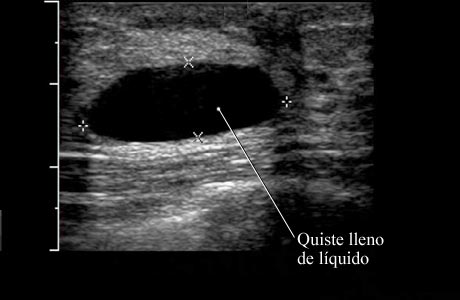

Ecografía de un quiste simple de seno